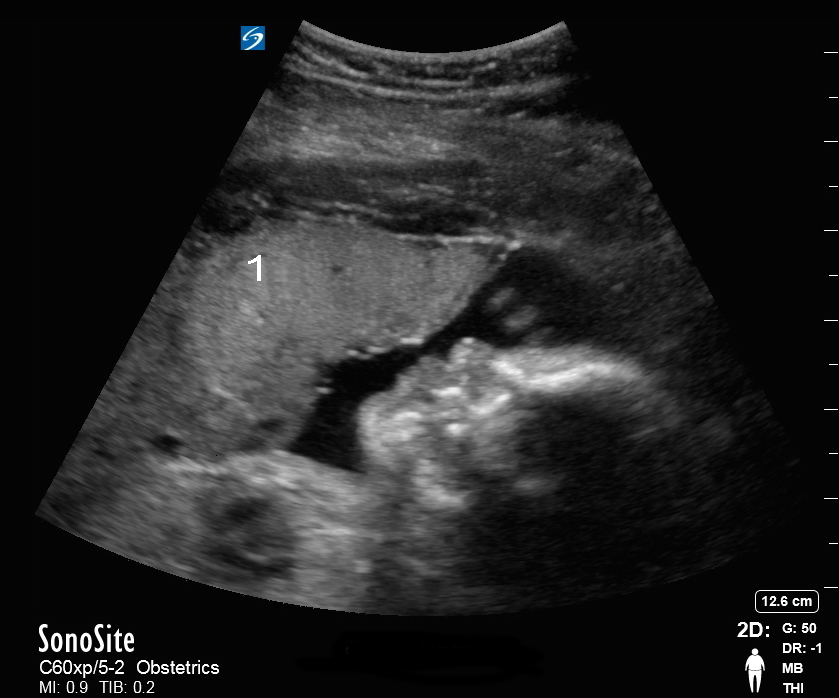

胎児骨盤のプロフィール画像

胎盤